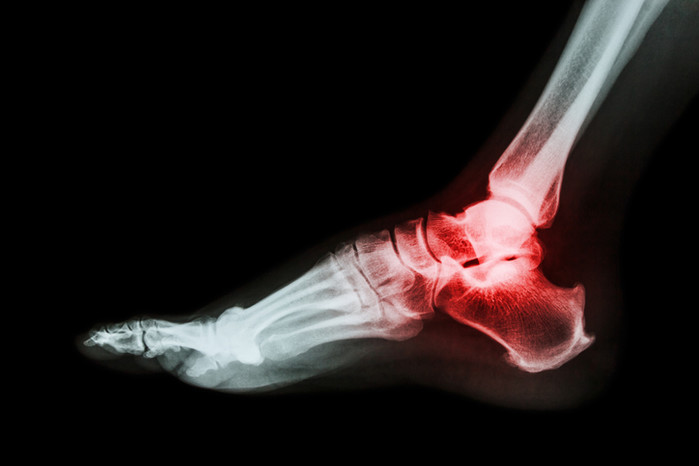

통풍 증상은 우리 몸에 있는 요산이 배설되지 않고 모여져 그로 인한 요산 결정이 발생해 발생하는 질환이다. 이렇게 발생된 요산 결정은 관절이나 연골에서 염증 및 통증을 동반한다. 초반에 나타나는 통풍의 증상은 대체로 엄지발가락에 나타나면서 시작되는 경우가 많다. 걸을 때 첫째 발가락에 통증이 느껴지다 부어오를 수 있다. 증상이 심화될수록 관절에 열감을 느끼고 붉게 변하거나 부기를 함께 느낄 수 있다. 증상이 심해지면 통증부위가 퍼지고 아픔을 느끼는 정도도 더 심해진다. 통풍증상이 존재하다가도 통풍 증상이 잠깐 사라질 수 있는데 이런 증상을 통풍이 완치됐다고 자부하면 안된다. 통풍을 방치하면 다양한 합병증을 불러올 수 있으니 조기치료가 중요하다.